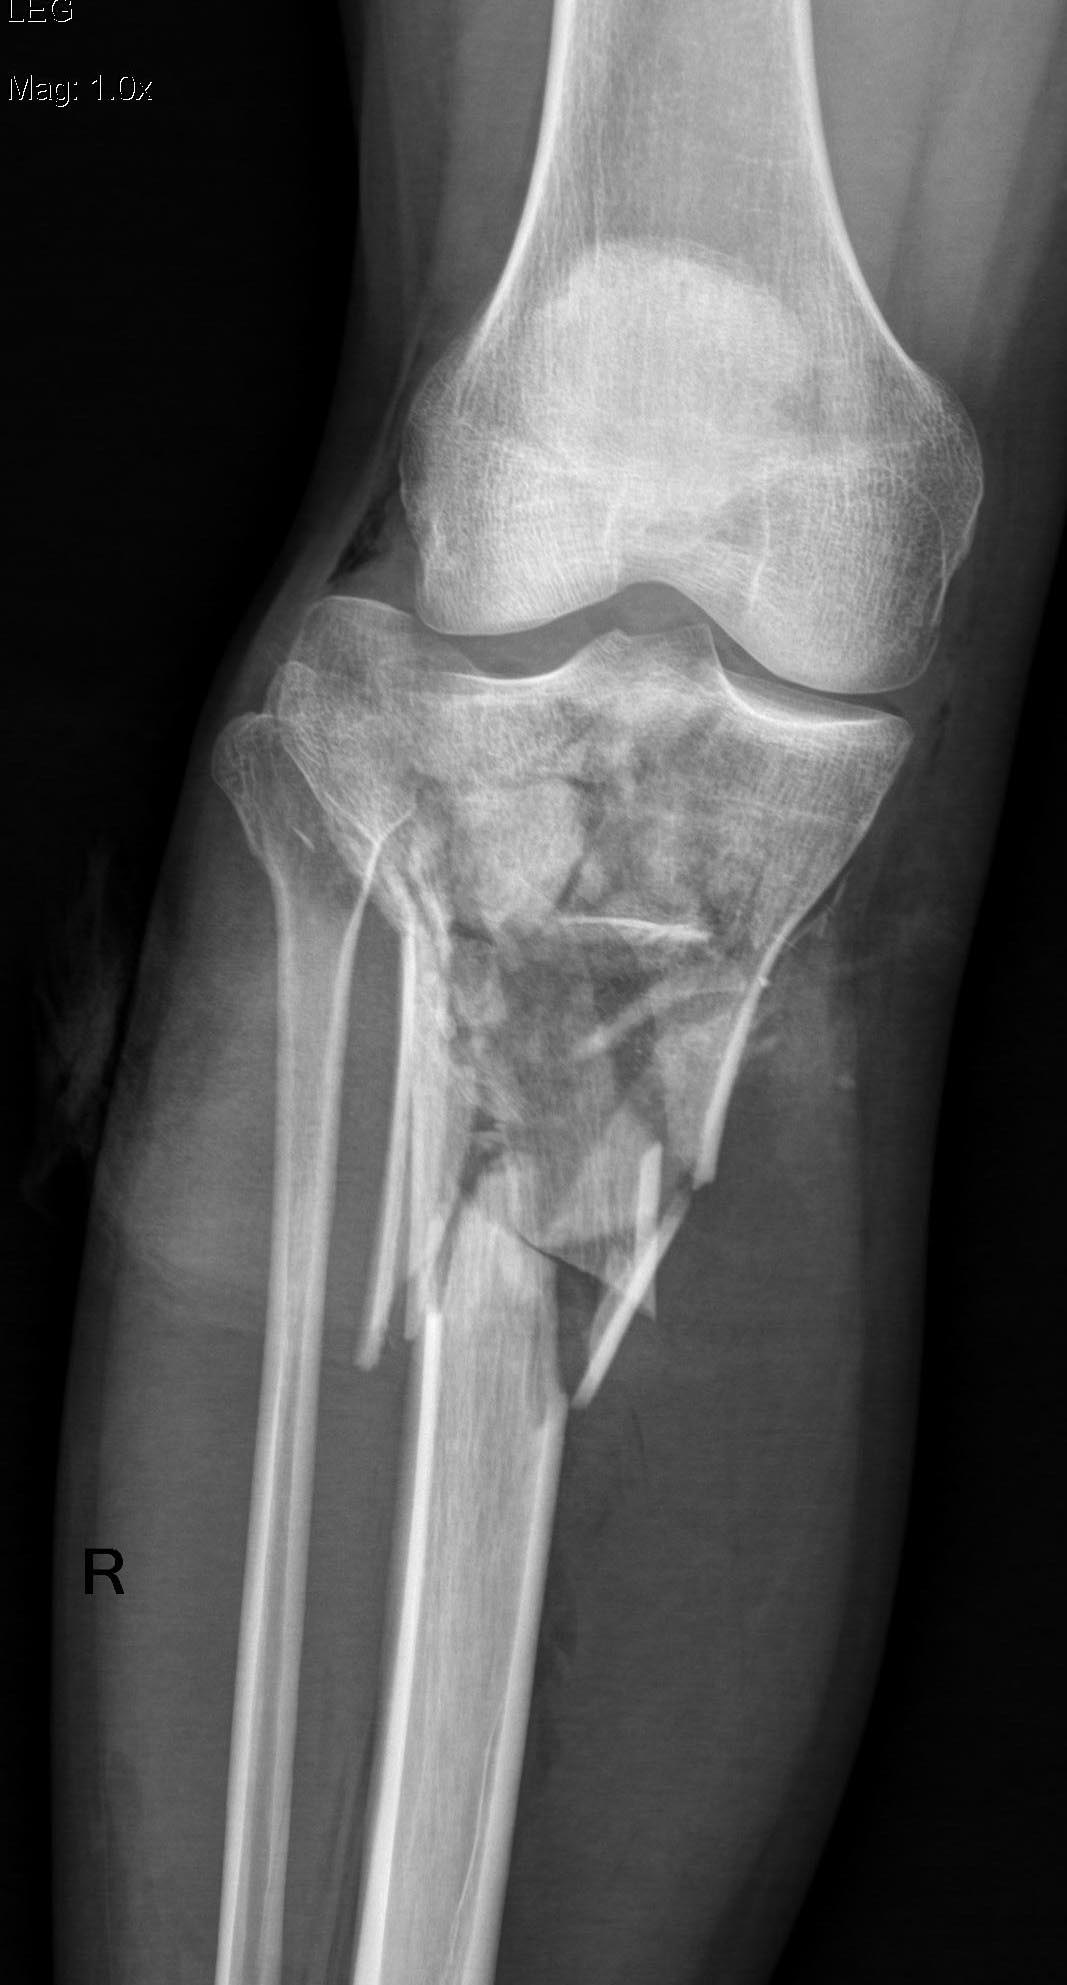

Имеется: Закрытый перелом диафиза левой локтевой кости. Закрытый оскольчатый перелом диафиза левой бедренной кости в средней трети. Открытые (3a-b) оскольчатые внутрисуставные переломы проксимального отдела обеих костей правой и левой голени. (см. снимки)

При поступлении выполнено: ПХО открытых перелом костей правой и левой голени, фиксация в аппаратах; фиксация перелома левой бедренной кости в аппарате; иммобилизация левого предплечья лонгетой.

Планируем: при неосложненном заживлении, остеосинтез правой большеберцовой кости пластиной; остеосинтез бедренной кости стержнем; локтевой кости пластиной.

Что делать с переломами костей левой голени пока не решили окончательно. Пока мнение коллег такое: оставить все как есть до заживления /консолидации и ортопедические проблемы с коленным суставом и укорочением (3-4 см) решать в отдаленном периоде – эндопротезирование (?).